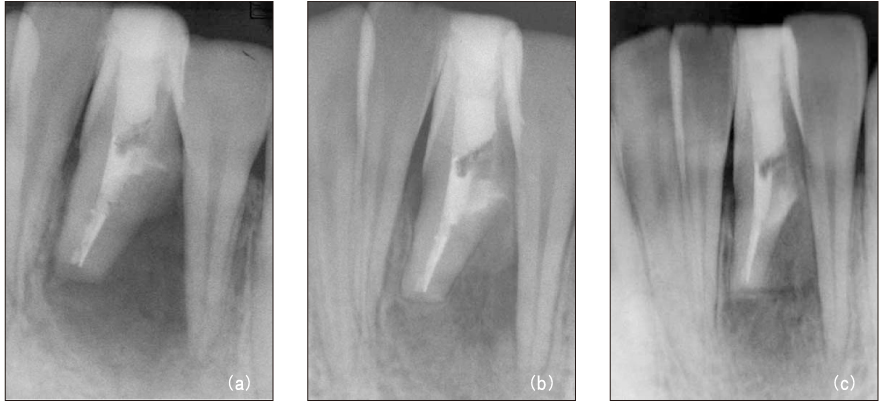

Figure 10

After intentional replantation (a), 3-month recall (b), 6-month recall (c) radiograph.

jkacd-31-161-g010.jpg

Figure 10 After intentional replantation (a), 3-month recall (b), 6-month recall (c) radiograph.

Figure 11 Diagnostic intraoral radiograph (a). By-passing with hand file (b) and canal obturation (c, d). 30-month recall (e): tooth is symptomless.